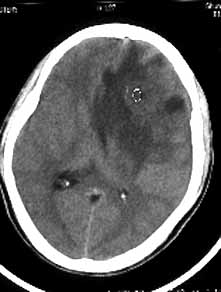

男性,36岁,头痛数年,近期伴有视蒙。

ct诊断:左额颞部脑膜瘤。